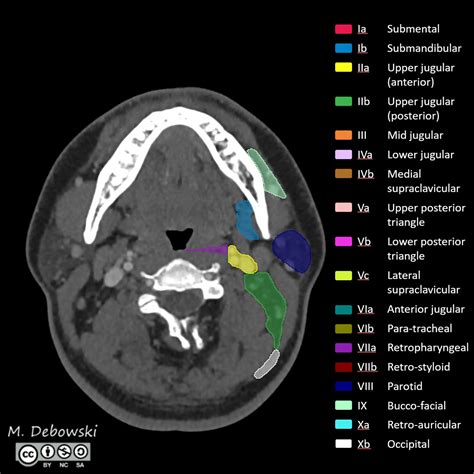

The neck is divided into several levels to facilitate the identification and classification of lymph nodes. This systematic approach is essential for accurate diagnosis and treatment planning. The neck lymph node levels are typically categorized into seven levels, each with specific anatomical boundaries and clinical significance.

Level I lymph nodes are located in the submental and submandibular regions. The submental nodes are found beneath the chin, while the submandibular nodes are situated below the lower jaw. These nodes drain lymph from the floor of the mouth, the tip of the tongue, and the lower lip. They are crucial for detecting infections or malignancies in these areas.

Level II lymph nodes are located along the upper third of the internal jugular vein. These nodes drain lymph from the nasopharynx, oropharynx, and the upper part of the larynx. They are important for evaluating conditions such as tonsillitis, pharyngitis, and cancers of the head and neck.

Level III lymph nodes are situated along the middle third of the internal jugular vein. These nodes receive lymph from the oral cavity, oropharynx, and larynx. They are often involved in the spread of malignancies from these regions and are critical for staging head and neck cancers.

Level IV lymph nodes are found along the lower third of the internal jugular vein. These nodes drain lymph from the larynx, thyroid gland, and lower part of the pharynx. They are significant in the evaluation of thyroid cancers and other malignancies in the lower neck region.

Level V lymph nodes are located in the posterior triangle of the neck, bounded by the sternocleidomastoid muscle, trapezius muscle, and clavicle. These nodes drain lymph from the scalp, posterior neck, and upper back. They are important for detecting infections and malignancies in these areas.

Level VI lymph nodes are situated in the anterior compartment of the neck, between the hyoid bone and the suprasternal notch. These nodes drain lymph from the thyroid gland, larynx, and central compartment of the neck. They are crucial for evaluating thyroid cancers and other malignancies in the anterior neck region.

Level VII lymph nodes are located in the superior mediastinum, below the suprasternal notch. These nodes drain lymph from the thyroid gland, larynx, and trachea. They are important for detecting malignancies that have spread from the neck to the mediastinum.